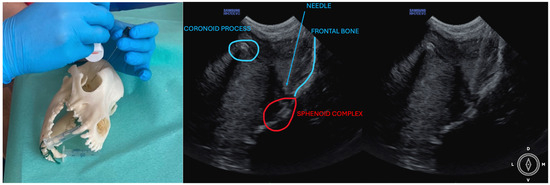

The ultrasound probe was positioned over the temporal region immediately caudal to the orbital ligament to obtain a transverse view of the caudal portion of the pterygopalatine fossa for both approaches. Slight tilting movements adjusted the probe until the following structures were identified: the frontal bone was observed as a hyperechogenic continuous line, which in the deep aspect of the pterygopalatine fossa showed an irregular structure consistent with the sphenoidal complex (optic canal, orbital fissure, and rostral alar canal). The coronoid process was also identified as a sharp, small, strongly reflective, hyperechogenic structure casting a strong acoustic shadow through the fossa (Figure 1 and Figure 2).

Description of the temporal approach: the needle was inserted using an in-plane approach from the medial aspect of the temporal region in a ventral direction until its tip was located close to the sphenoidal complex (Figure 1), where the calculated volume was injected.

Figure 1. Position of the probe and needle. Ultrasound image of the temporal approach, where the anatomic landmarks can be identified. The microconvex ultrasound probe is placed on the temporal region, caudally to the orbital ligament, in a transversal position.